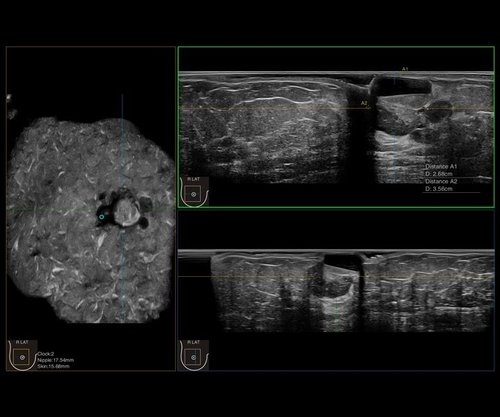

Das IBUS 60 ist ein intelligentes Brust-Vollvolumen-Ultraschallsystem der Marke SIUI.

Das IBUS 60 zeichnet sich durch Sicherheit und Komfort aus. Es bietet ein hochauflösendes Bild und reduziert somit Fehldiagnosen, was ideal für die Brustuntersuchung ist, insbesondere bei einer dichten Brust.